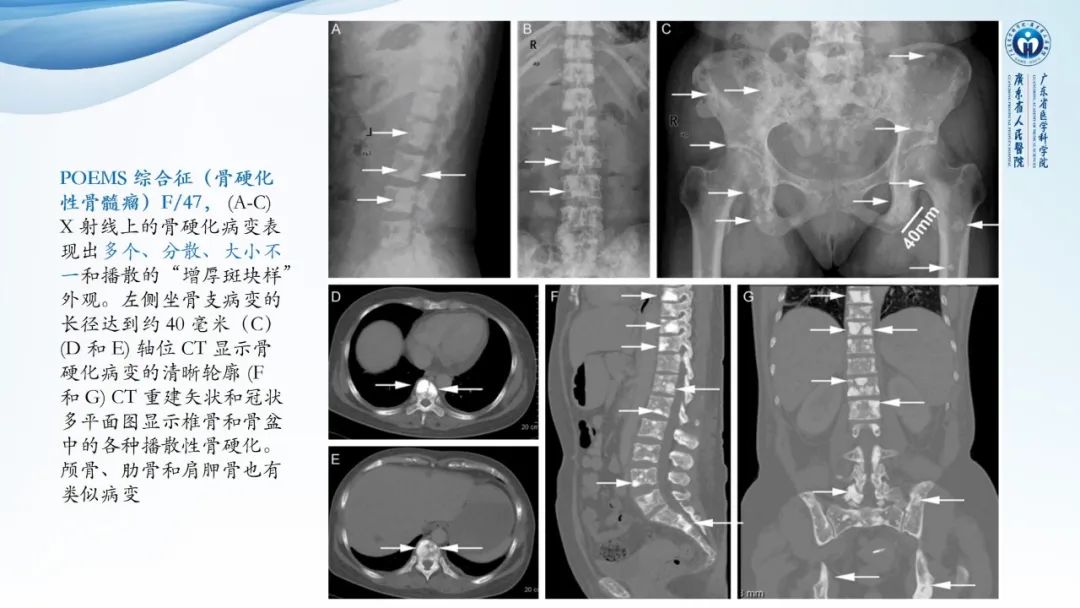

【病例】一例表现为弥漫中轴骨骨质增生硬化病变讨论-3